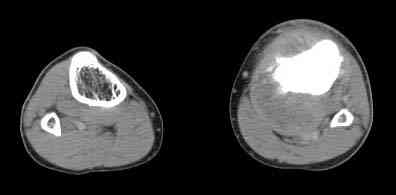

важаемые коллеги! Поступил больной 22 лет. Болен с января 2006 - появились боли в области верхнейтрети голени. При первичном осмотре в поликлинике был заподозрен первично-хронический остеомиелит - осмотрен гнойным хирургом - произведена биосия . Заключение - хондросаркома. Осмотрен онкологом - с учетом характера опухоли - химиотерапия, лучевое лечение не показано. Предложена либо ампутация, либо решение вопроса о возможности выполнения органосохраняющей операции. При обращении к нам произведена сцинтиграфия скелета - зоны гиперфиксации РФП: верхняя треть голени- 960%, нижняя треть бедра - 380%, Дистальный метафиз голени и затылочная область - 140%. В легких - метастазов нет. Произведена КТ (картинки в приложении). Учитывая абсолютную нестыковку рентгенологических и морфологических данных повторно биопсия. Выявлено, что первичная биопсия выполнялась из поверхностной параоссальной зоны - там локализованы хрящеподобные массы, далее очень плотная кость без хрящевых участков - биоптат взят фрезой с большим трудом. Морфологического заключения пока нет. Хотелось бы узнать Ваши варианты диагноза и соответственно тактику.